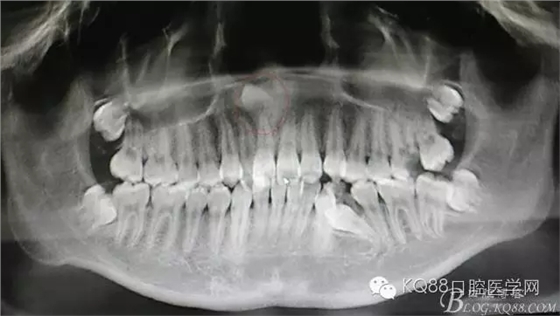

圖1.CBCT全景片重建檢查:11根尖區(qū)上方有一倒置多生牙